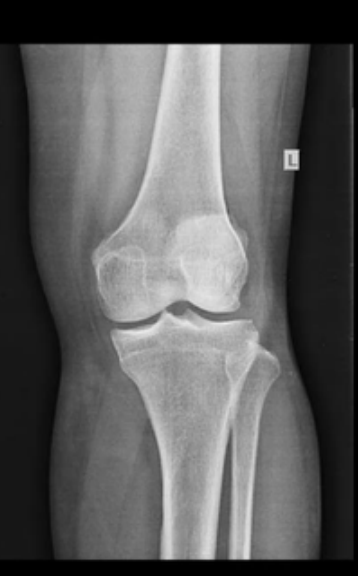

Perempuan, 43 tahun, datang ke puskesmas dengan keluhan nyeri pada lutut kiri sejak 6 bulan yang lalu. Nyeri dirasakan hilang timbul dan terasa seperti tertusuk-tusuk. Keluhan biasanya timbul pada saat naik turun tangga, saat perpindahan posisi dari duduk lalu berdiri ataupun sebaliknya. Nyeri berkurang jika istirahat. Pasien juga mengeluh kaku pada lutut kiri terutama saat bangun tidur.

Apakah struktur anatomi yang terlibat dan apa kelainannya?

Cairan Synovial pada Articulatio Genu => Osteoarthritis